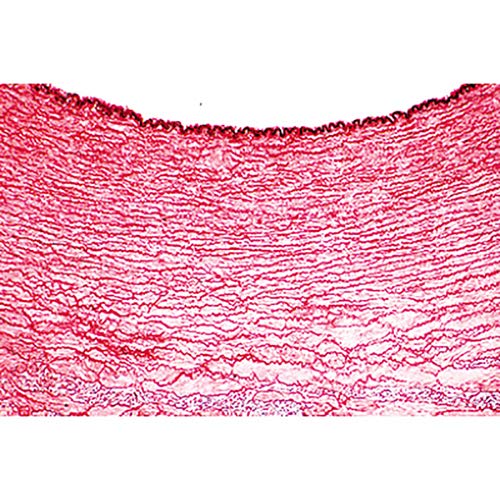

Microscope Slides: 1(d). Trachea, cat, t.s. 2(e). Lung, human t.s. 3(c). Blood, human, Wright stained smear 4(c). Artery, human, t.s., elastica stained